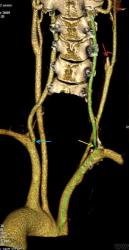

Мужчина, 62 года. Перенес ишемический инсульт в бассейне правой средней мозговой артерии.

На КТ-ангиографии выявлена окклюзия правой внутренней сонной артерии в области развилки в виде паламени свечи (красная стрелка), стеноз высокой степени в устье правой вертебральной артерии (желтая стрелка), небольшой перегиб в устье левой вертебральной артерии (голубая стрелка).